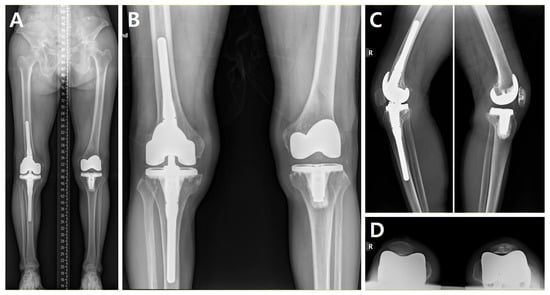

| 1 | F/68 | Left | 2.3 | + | + | + | 15.4 | +/16 | + | + | ||||

| 2 | F/68 | Right | 20.8 | + | + | + | + | 26.1 | −/18 | + | + | + | + | VY-Q |

| 3 | F/76 | Left | 10.1 | + | + | 15.6 | −/22 | + | + | + | ||||

| 4 | F/76 | Right | 10.2 | + | + | 12.3 | −/16 | + | + | |||||

| 5 | F/60 | Left | 10.4 | + | + | + | + | 27.1 | −/11 | + | + | + | Q-snip | |

| 6 | M/66 | Right | 11.0 | + | 15.7 | +/18 | + | + | ||||||

| 7 | F/64 | Left | 0.4 | + | + | 19.1 | +/17 | + | + | |||||

| 8 | F/64 | Right | 0.73 | + | + | + | 24.5 | +/20 | + | + | ||||

| 9 | F/71 | Right | 4.6 | + | + | + | 20.5 | +/14 | + | + | ||||

| 10 | F/71 | Left | 5.0 | + | + | 16.4 | +/13 | + | + | |||||

| 11 | F/70 | Right | 2.3 | + | + | + | + | 23.7 | +/20 | + | + | |||

| 12 | M/57 | Right | 17.6 | + | + | + | 20.2 | −/22 | + | + | + | Q-snip | ||